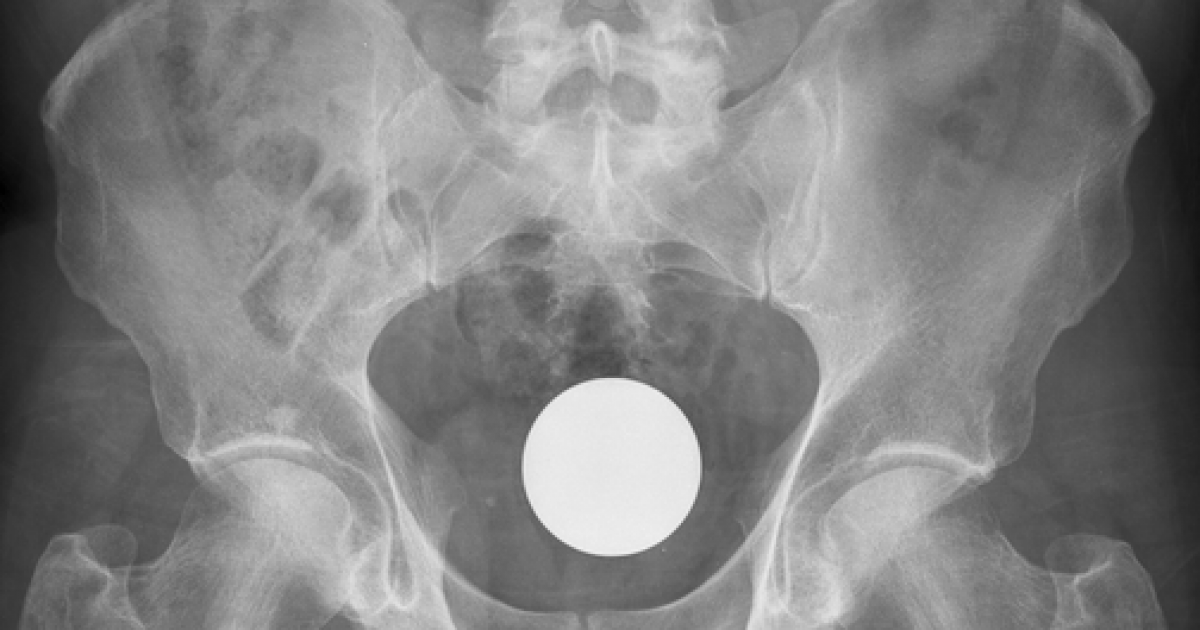

NASCONDEVA COCAINA NEL RETTO. PRATOLANO INCASTRATO DALLA RADIOGRAFIA. Un uomo di 46 anni di Pratola Peligna è stato arrestato con l'accusa di spaccio di sostanze stupefacenti. Aveva nascosto 7 grammi di cocaina nel retto scoperti dalla polizia dopo un controllo radiografico presso l'ospedale di Aversa, che ha consentito di individuare il pacchetto nel corpo dell'uomo. L’uomo è stato quindi rinchiuso presso il carcere di Napoli-Poggioreale.